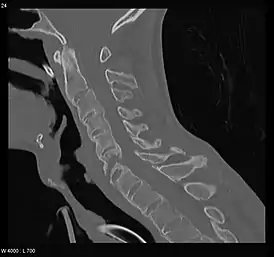

Перелом позвоночника

Перелом позвоночника — патологическое состояние, возникающее в ходе нарушения анатомической целостности костей позвоночника. Происходит под воздействием силы, вызывающей резкие и чрезмерные сгибания позвоночника или при непосредственном воздействии силы (травма). Все переломы позвоночника можно разделить на ряд групп в зависимости от положения перелома и его характера:[2]

- Перелом шейного отдела позвоночника

- Перелом грудного отдела позвоночника

- Перелом поясничного отдела позвоночника